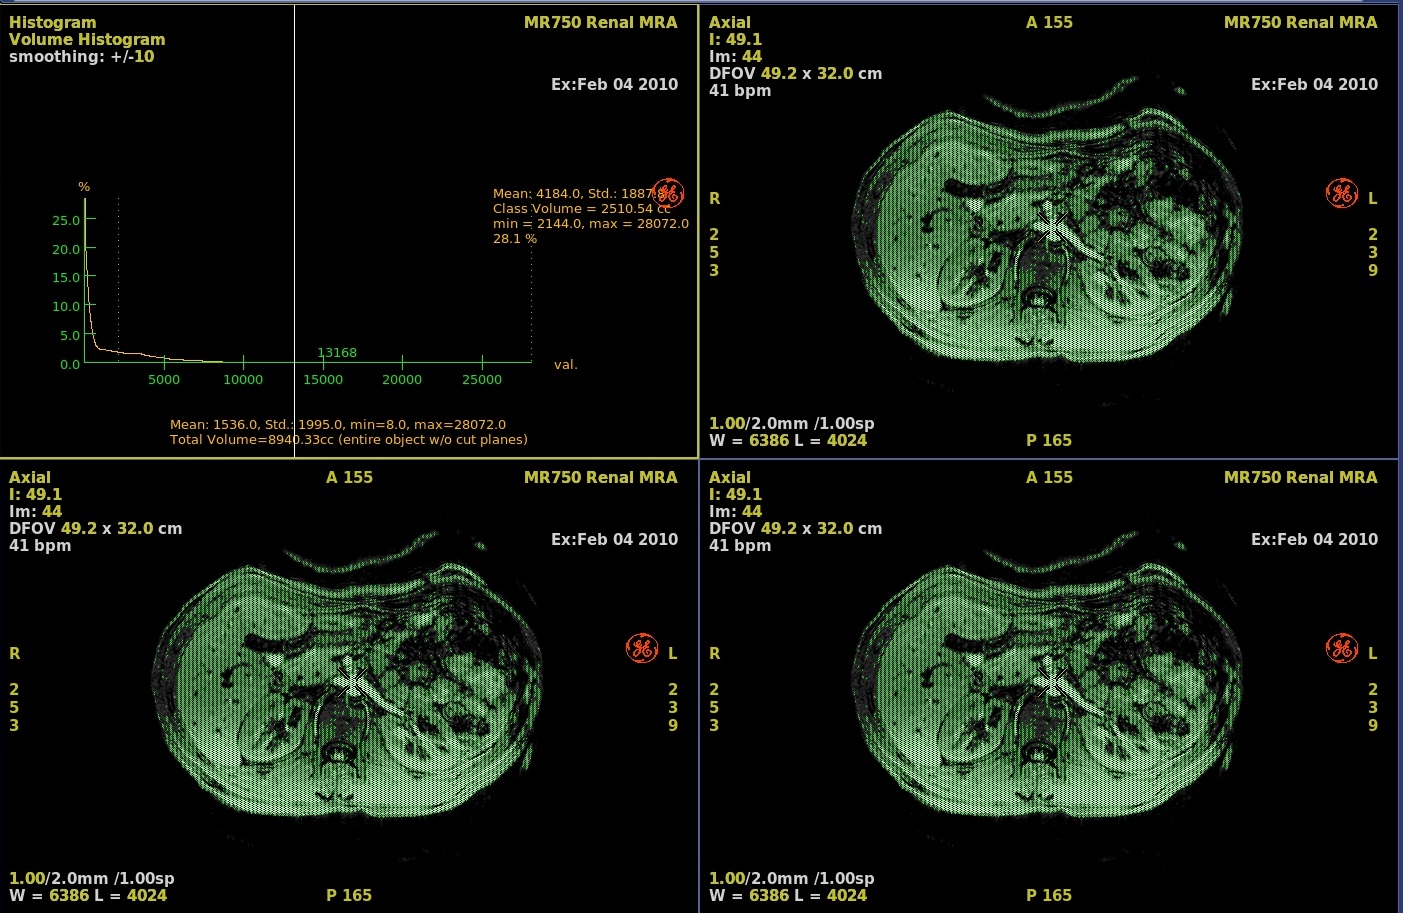

Figure 2. Example of Threshold narrowed

- On the histogram graph, click and drag the green dashed line to adjust the threshold.

2. Voxel reference line Move the voxel reference line to select a class of voxels. 3. Voxel class statistics A voxel class refers to a range (class) of voxels whose values are specific to a certain anatomical feature (e.g. bone surrounded by muscle, or a tumor surrounded by healthy tissue). 4. Class boundaries

Class boundary lines located on both sides of the center white line, mark the upper and lower limit of a class (range) of voxel values around the voxel reference line whose values are specific to a certain anatomical feature (e.g. bone surrounded by muscle, or a tumor surrounded by healthy tissue). These boundaries are calculated automatically and displayed as green thin dotted lines. You can move them manually to delimit an exact range of voxel values. The software analyzes the peaks and valleys of the histogram curve and determines the voxel class around the current voxel reference line from the changes in slope (the inflection points) of the histogram curve. Set the smoothing value as required before using the class boundaries.

5. Statistics Statistics about the voxel values (mean, standard deviation, maximum, and minimum) within the class defined by the boundary lines, and the computed value of the corresponding surface area or volume.